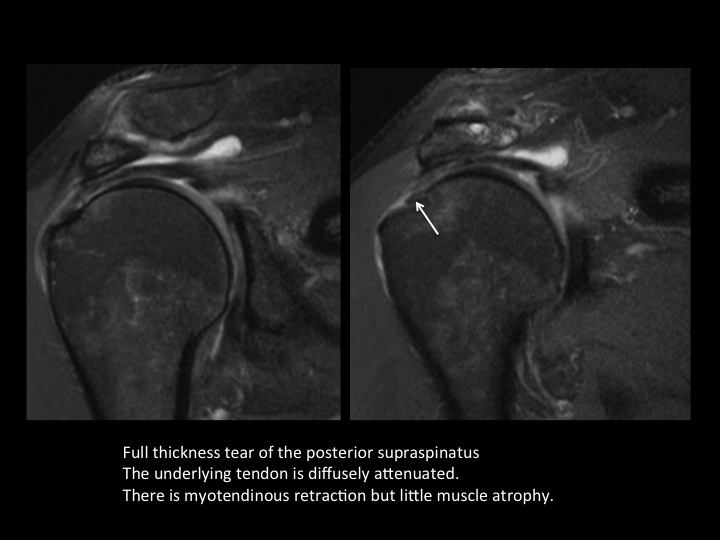

There is diffuse thinning of the suprapinatus tendon with full thickness tear posteriorly; the myotendinous jxn is retracted but there is little supraspinatus atrophy. There is a contiguous partial articular surface delaminating tear of the IST extending to the myotendinous jxn, best demonstrated in the BLO sequence. Axial images show partial articular surface delaminating tear of the subscap (note the extreme ER of the arm) with medial subluxation of the LHBT as there is a type 3 Bennett biceps pulley lesion. There is a low lying os acromiale with a subacromial enthesophyte and degen changes at the synchondrosis. Reference article.